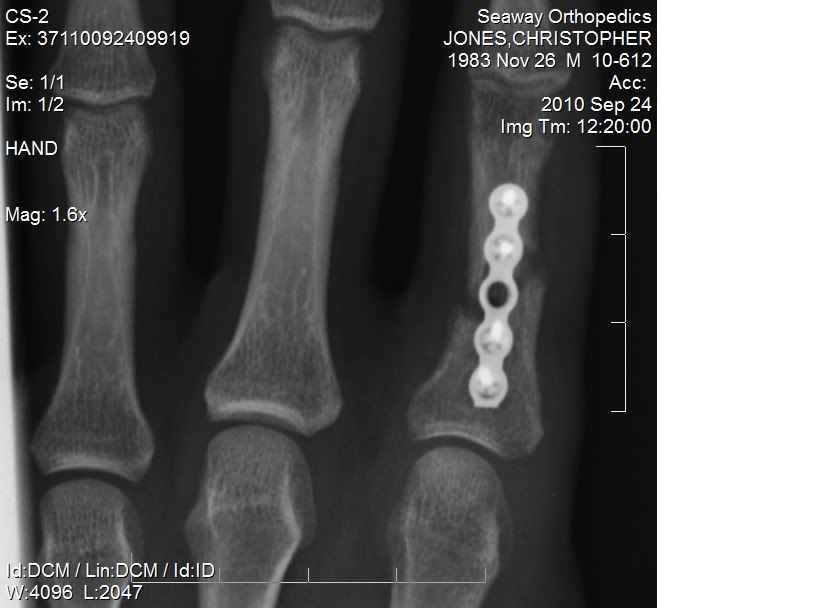

sorry for the crappy cell pic, but you can see the plate and where there is no bone formation at the break.